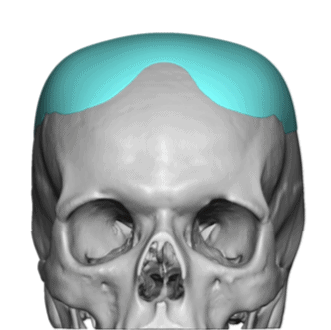

Patient 28

Desire for rounder shape to the top of the head from a congenital parasagittal deficiency skull shape.

Custom skull implant designed to fill in the parasagittal deficiencies.

Desire for rounder shape to the top of the head from a congenital parasagittal deficiency skull shape.

Custom skull implant designed to fill in the parasagittal deficiencies.